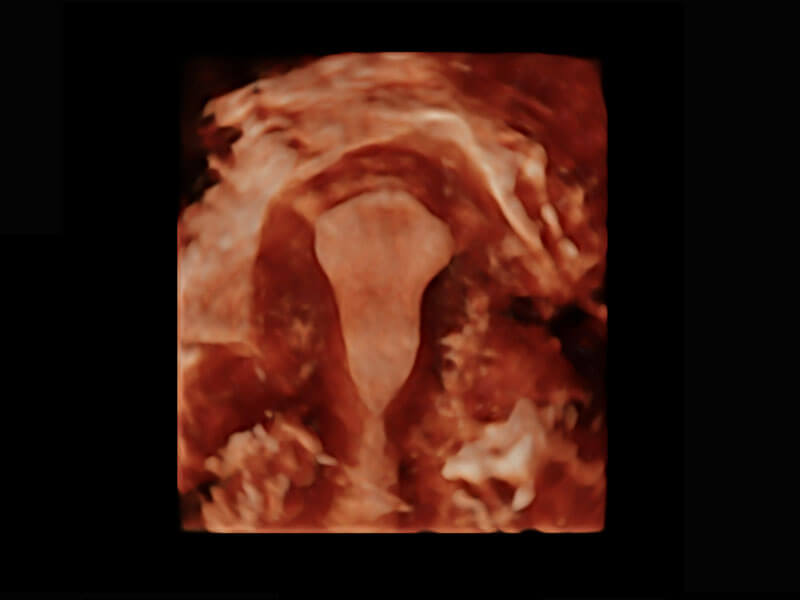

腔内三维-光影成像

高分辨率容积成像-早孕胎儿